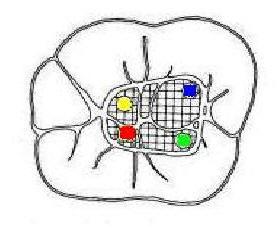

Primer Molar Inferior Esta pieza dentaria es la más voluminosa de la arcada. Posee por general dos raíces bien definidas una mesial y otra distal, ambas aplanadas en sentido mesiodistal. La raíz mesial presenta una curvatura acentuada, mientras que la distal puede ser algo curva o recta. Cuando tiene tres conductos el mas amplio es el distal con una sección oval y su curvatura es suave o recta. Si presenta cuatro conductos la raíz distal contendrá dos de ellos y son de diámetro más pequeño y en caso de presentar dos conductos, ambos son amplios. Segundo Molar Inferior Es de menores proporciones que el primer molar y sus raíces en general son dos y diferenciadas como en el primer molar ,así como también pueden presentarse fusionadas parcial o totalmente. |